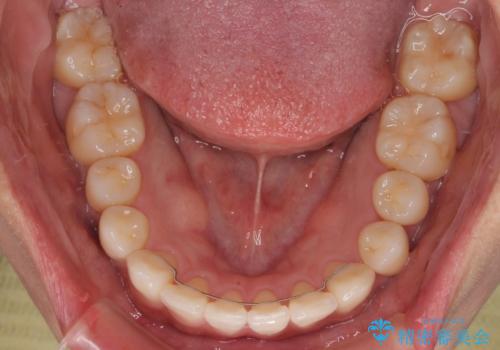

初診時、上下顎ともに歯列の不正が認められ、特に左下の小臼歯が大きく歯列から外れている状態でした。その影響により、下顎の正中が左側へシフトしており、見た目だけでなく噛み合わせにも影響が出ていました。